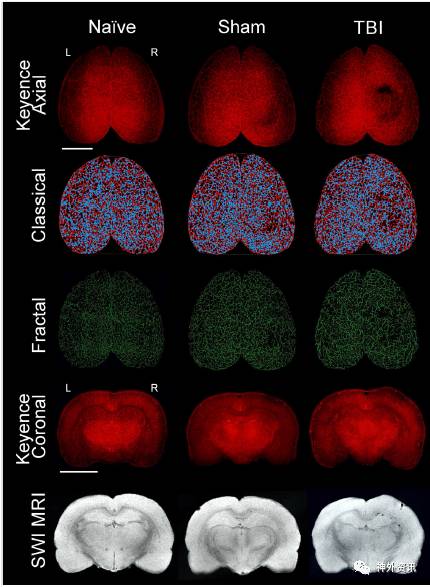

该研究将实验大鼠分为三组,naïve组、sham组和TBI组,每组5-6只。通过荧光显微镜观察实验鼠在TBI后染色的脑皮质血管,分析皮质血管网络的特征,包括血管连接数量以及血管长度。实验结果显示,与sham组相比,TBI组双侧大脑半球的皮质血管连接点以及血管长度均降低(图1、2),分别下降34.4%和21.5%。应用几何模型分析血管的生物性复杂度,发现峰度、峰值频率和偏度均降低,分别下降33%、16%和13%(图3、4)。

图1. naïve组大鼠脑部无血管破坏,sham组因开颅造成脑血管轻微改变,TBI组脑血管破坏明显。

图2. sham组大鼠开颅区附近脑血管染色均匀,TBI组在损伤处脑血管明显减少。